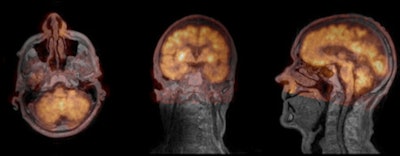

| Fusion of ultrashort-echo-time (UTE) MR image (gray; TE = 0.09 sec) and smoothed PET image (orange). PET data attenuation-corrected using UTE triple-echo MR data. From left to right, transaxial, coronal, sagittal cross-sections. Method from Berker et al, Journal of Nuclear Medicine, May 2012, Vol. 53:5, pp. 796-804. |